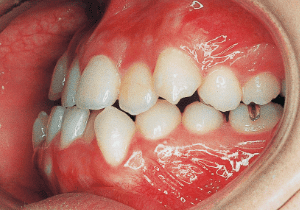

12 Before Phase 2 Treatment 10-26-’96 15 years 3 month

13 Before Phase 2 Treatment 10-26-’96

14 Before Phase 2 Treatment 11-6-’96

15 Beginning of 2nd Phase 1-29-’97 15 years 6 month

Although early treatment improved the slight deviation observed during the deciduous dentition stage, it became apparent that the deviation increased with age, eventually exceeding the limits of treatment. This appears to be an innate deviation, and the developmental pattern observed in this case seems to disregard the occlusion. Four first premolars were extracted (15), crowding was corrected and space closure was performed (16), and surgical intervention improved the deviation (17).